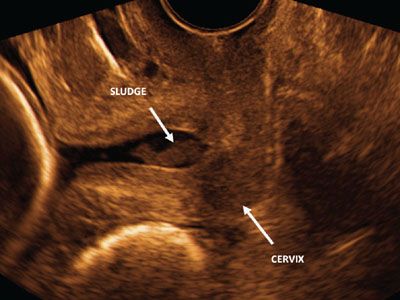

нсвагинальное узи шейки

Трансвагинальное узи шейки 114 фотографий